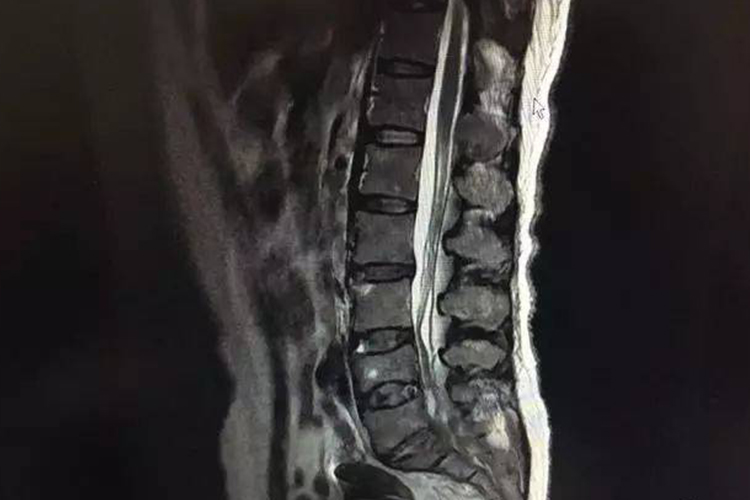

早期乳腺癌已有血运转移,癌细胞可直接侵入血液循环而致远处转移。最常见的远处转移依次为骨、肺、肝。乳腺癌转移至骨、肺、肝时,可出现相应的症状,如骨痛、咳血、肝区疼痛等。